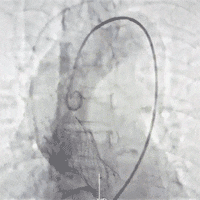

术中影像

瓣膜释放完毕

术后造影及超声提示未见反流无瓣周漏,瓣膜植入位置良好,术后即刻基本无压差,术后未出现相关并发症,手术圆满成功。